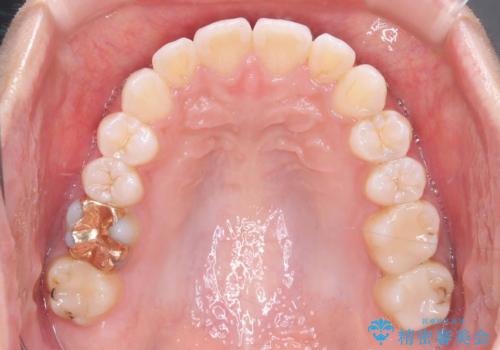

- 歯の捻じれやデコボコを主訴にご来院された患者様です。

矯正治療の精密検査を行った結果、非抜歯(歯を抜かない)矯正治療を選択いたしました。

治療は、白いコーティングが施されたワイヤーを使用した審美性の高い装置にて行っています。